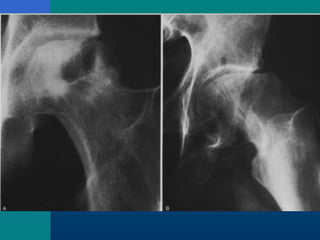

SLIPPED CAPITALSLIPPED CAPITAL

FEMORAL EPIPHYSISFEMORAL EPIPHYSIS

A true adolescent problem

Gradual or acute slip

through the capital

femoral physis

Investigations

X-ray – AP

Frog leg lateral view

( contraindicated when

suspecting acute slip)